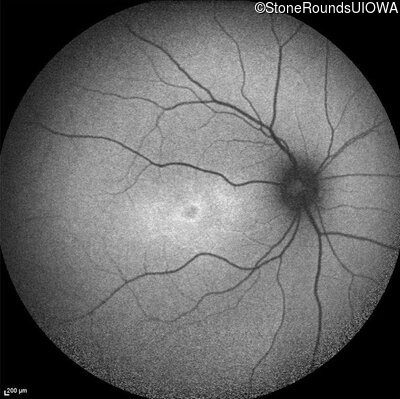

Age at visit: 17 years

OD OS

This 17 year old female first noted problems with her visual acuity around age 13 when she had trouble seeing the projector from the back of the classroom.